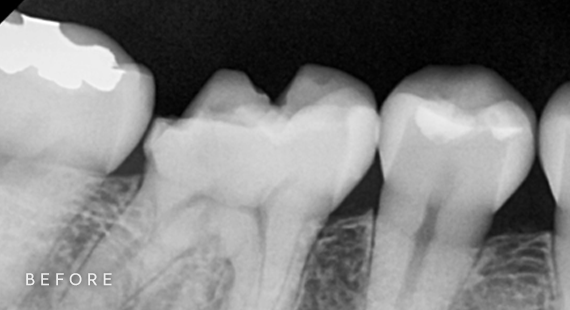

충치치료